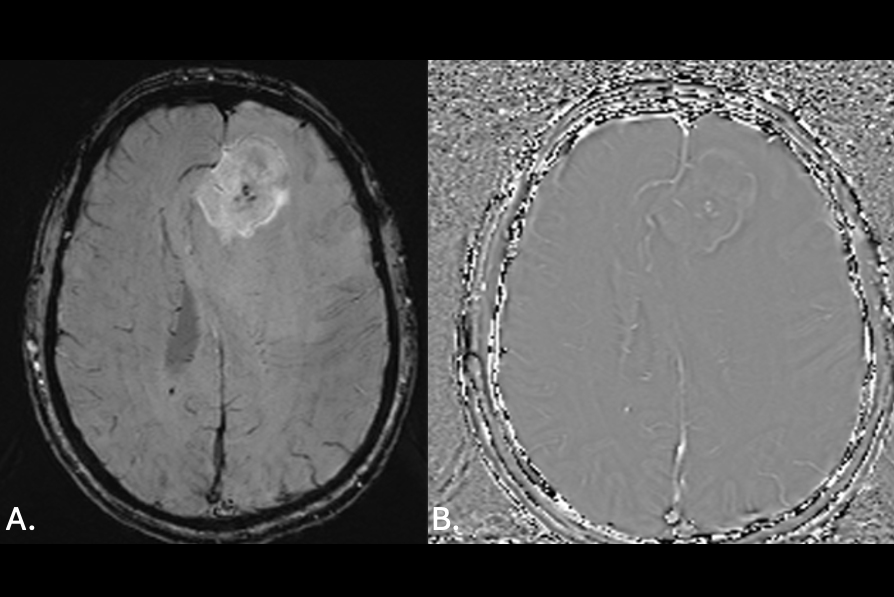

The company, whose head office is in Utrecht, The Netherlands, is developing BoneMRI, a radiation-free bone imaging technology.